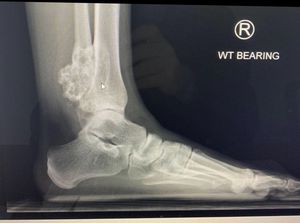

Xray - hard mass on lateral ankle

Osteochondroma